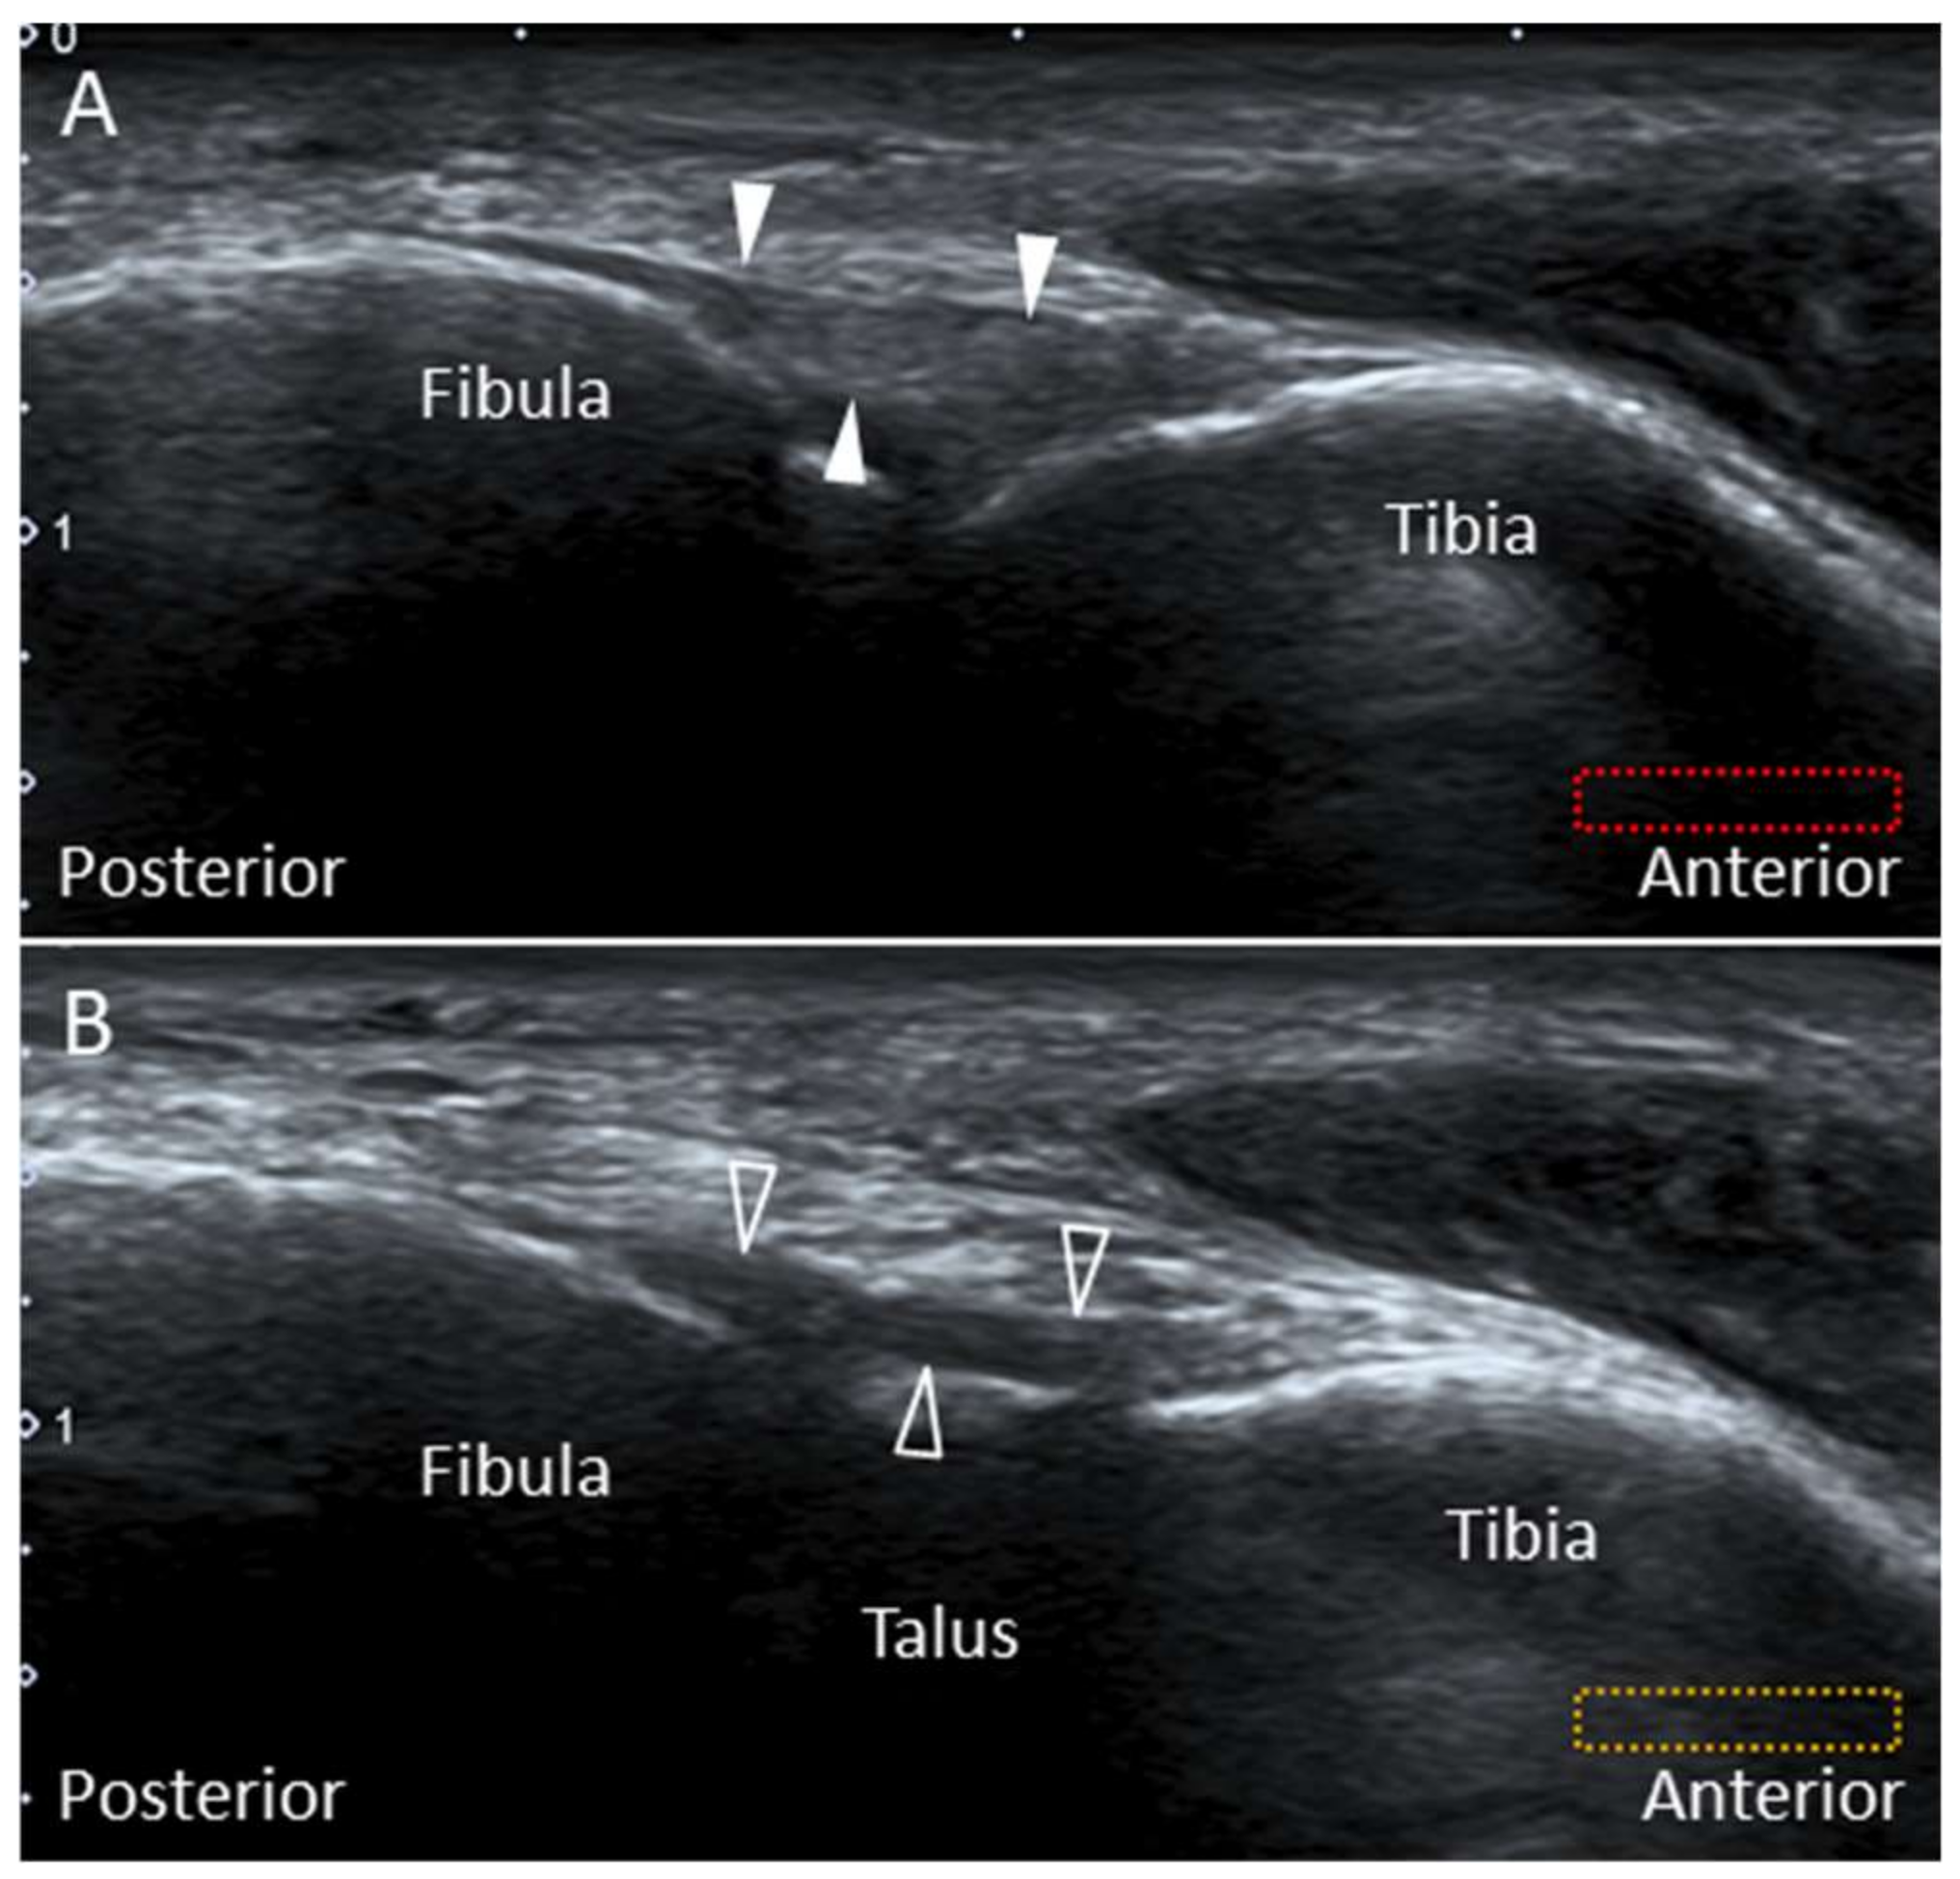

2.2. Posterior Inferior Tibiofibular Ligament

2.2.1. Anatomy

2.2.2. Scanning Technique

2.2.3. Clinical Relevance

2.3. Intermalleolar Ligament

2.3.1. Anatomy

2.3.2. Scanning Technique

2.3.3. Clinical Relevance